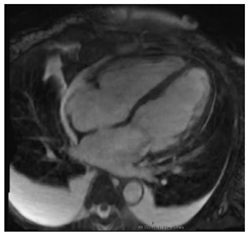

| CMR Parameter | Key CMR Findings | Illustrative Example |

|---|---|---|

| Cardiac Structure and Function | Dilated ventricular chambers with reduced systolic function in later stages | ![]() |

| T1 time | Short native T1 time | ![]() |

| T2 Time | Short T2 time | ![]() |

| T2* Time | Short T2* time, which inversely correlates with myocardial iron content

| ![]() |

| LGE | Patchy areas of LGE can be seen secondary to replacement fibrosis | ![]() |